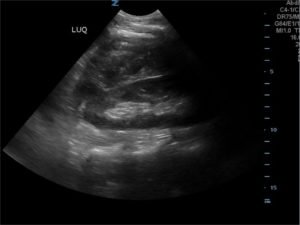

FAST Exam to Diagnose Subcapsular Renal Hematoma

A 49-year-old male presents for evaluation of hematuria and left flank pain after mechanical fall down stairs four days ago. Point-of-care ultrasound (POCUS) focused assessment with sonography in trauma (FAST) exam demonstrated subcapsular renal hematoma. Once a subcapsular hematoma is recognized the provider should keep in mind that this condition may be managed conservatively in patients with two normally functioning kidneys, but may require urgent intervention if the patient is at risk for significant renal disease, such as a single kidney. The use of bedside ultrasound can expedite diagnosis and care for these patients, and allow proper consultants to be contacted early. Some consultants that may need to be consulted include nephrology, urology, and/or internal medicine. This case report emphasizes the utility of the FAST exam for patients presenting for non-acute trauma. The FAST exam can be utilized not only to identify free fluid in the abdomen and pelvis but also to visualize organs and the surrounding tissues for abnormalities after a trauma.